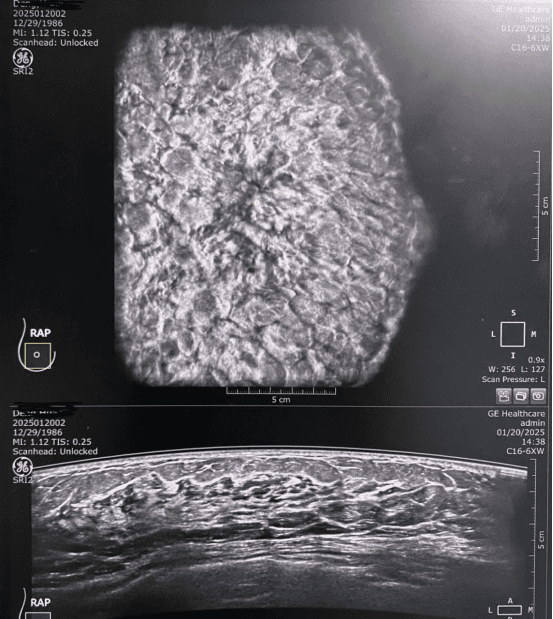

宋宏萍教授是国内超声医学领域的知名专家,尤其在乳腺超声诊断方面造诣深厚。活动中,她重点介绍了自动乳腺容积超声成像技术的原理、优势及临床应用。宋教授指出,ABUS技术能够提供更清晰、更立体的乳腺组织图像,有助于早期发现乳腺病变,显著提高诊断准确率,为乳腺疾病的精准诊疗提供了有力支持。

理论授课环节,宋宏萍教授结合丰富的临床案例,深入浅出地讲解了自动乳腺容积超声在乳腺疾病诊断中的应用价值。她强调,ABUS技术可广泛应用于乳腺癌的早期筛查、乳腺良恶性结节的鉴别诊断以及乳腺癌新辅助化疗疗效的评估等领域,为临床制定个性化治疗方案提供了重要依据。

疑难病例会诊:开拓思路,共解难题

此外,宋教授还参与了我院超声科的疑难病例会诊,与我院医生共同探讨了多例疑难乳腺病例的诊断思路和治疗方案。她渊博的学识和丰富的临床经验为疑难病例的诊治提供了新的思路,令我院医生受益匪浅。